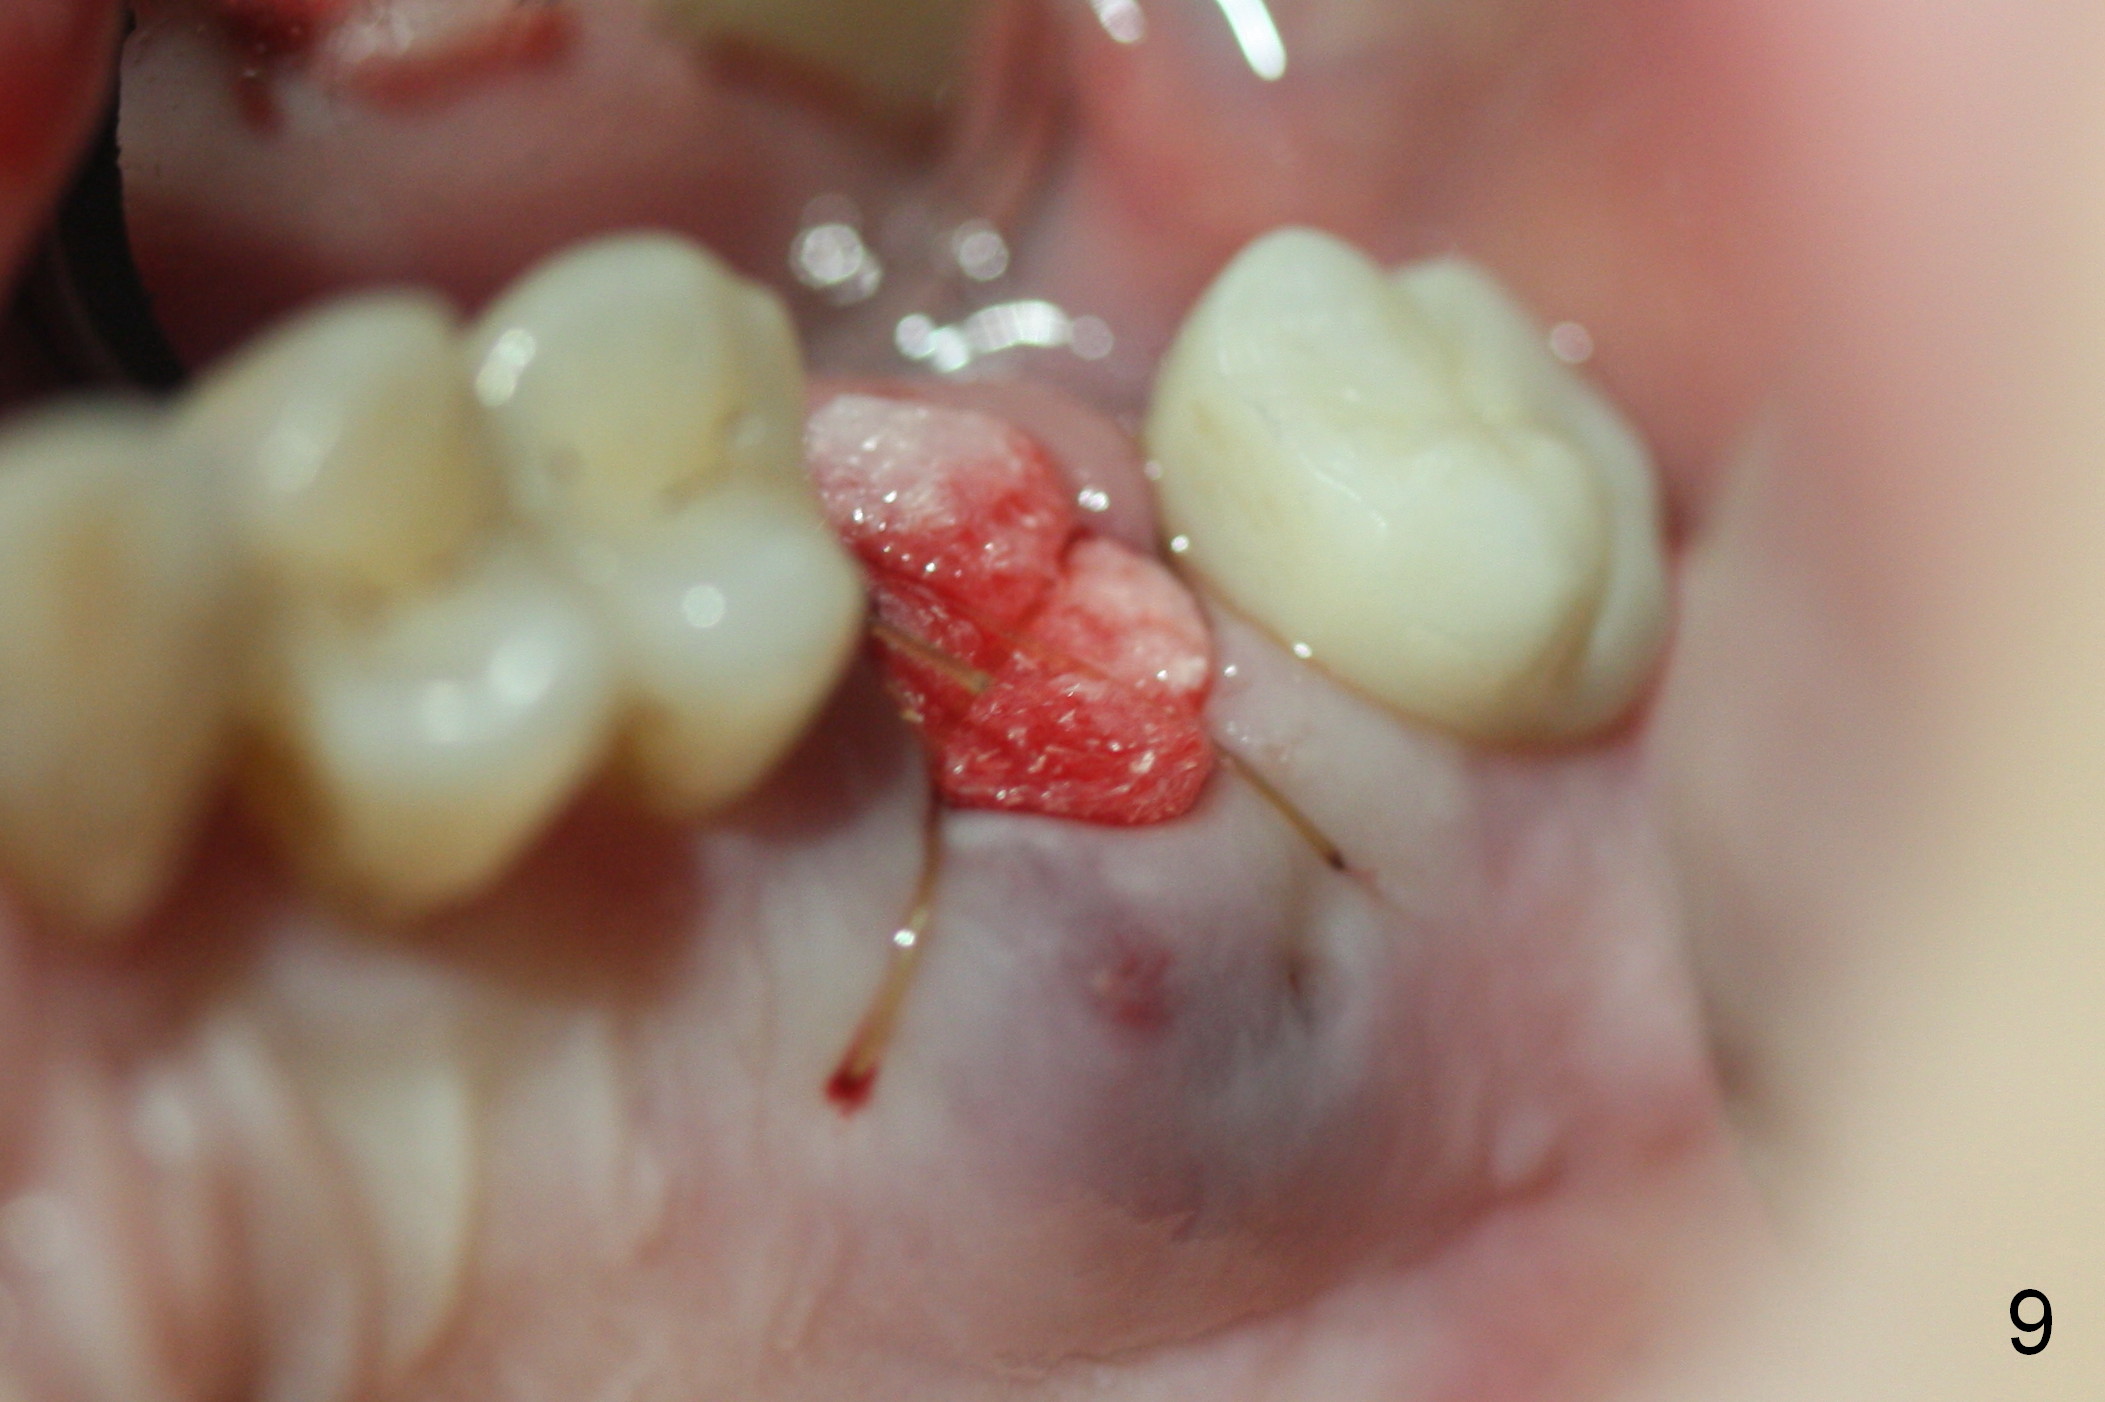

Serrated curette is used to remove granulation tissue mainly from large palatal socket, followed by copious irrigation, and placement of Clindamycin gauze x2 in the sockets. There is apical perforation of the MB socket. In the deep portion of each socket placed is ~.03 CANCELL Oss (Mineralized Cancellous Human Allograft, distributed by Impladent LTD, .850-1 mm, 03-0494763, Product Code 06412201) and equal amount of Osteogen into socket (Fig.8 red circles), covered with Osteogen plug (20x10 mm, Fig.8 green outline). The latter is fixed in placed by 4-0 Chromic gut suture (figure-8, Fig.9), followed by perio dressing, 2x2 gauze, hemastatic.

There is no palatal erythema or edema 9 days post extraction (Fig.10 *) with shrinkage of the socket opening. The Osteogen plug remains in place (Fig.11 P). The patient will return for implant placement 6 months post socket preservation.